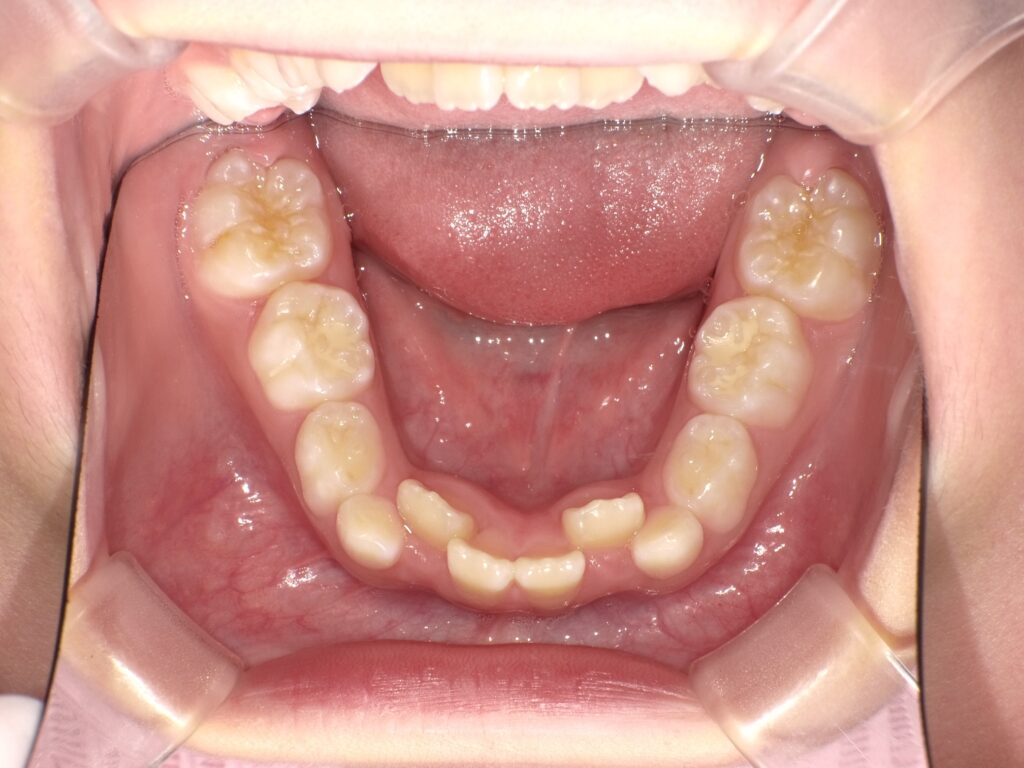

① 開咬

前歯が上下でかみ合わず、隙間があく状態。発音や咀嚼に影響することがあります。

② 上顎前突

上の前歯が前方に傾斜しやすくなります。

③ 上顎が狭くなる

常に指が入ることで舌の位置が下がり、上あごの横幅が狭くなることがあります。